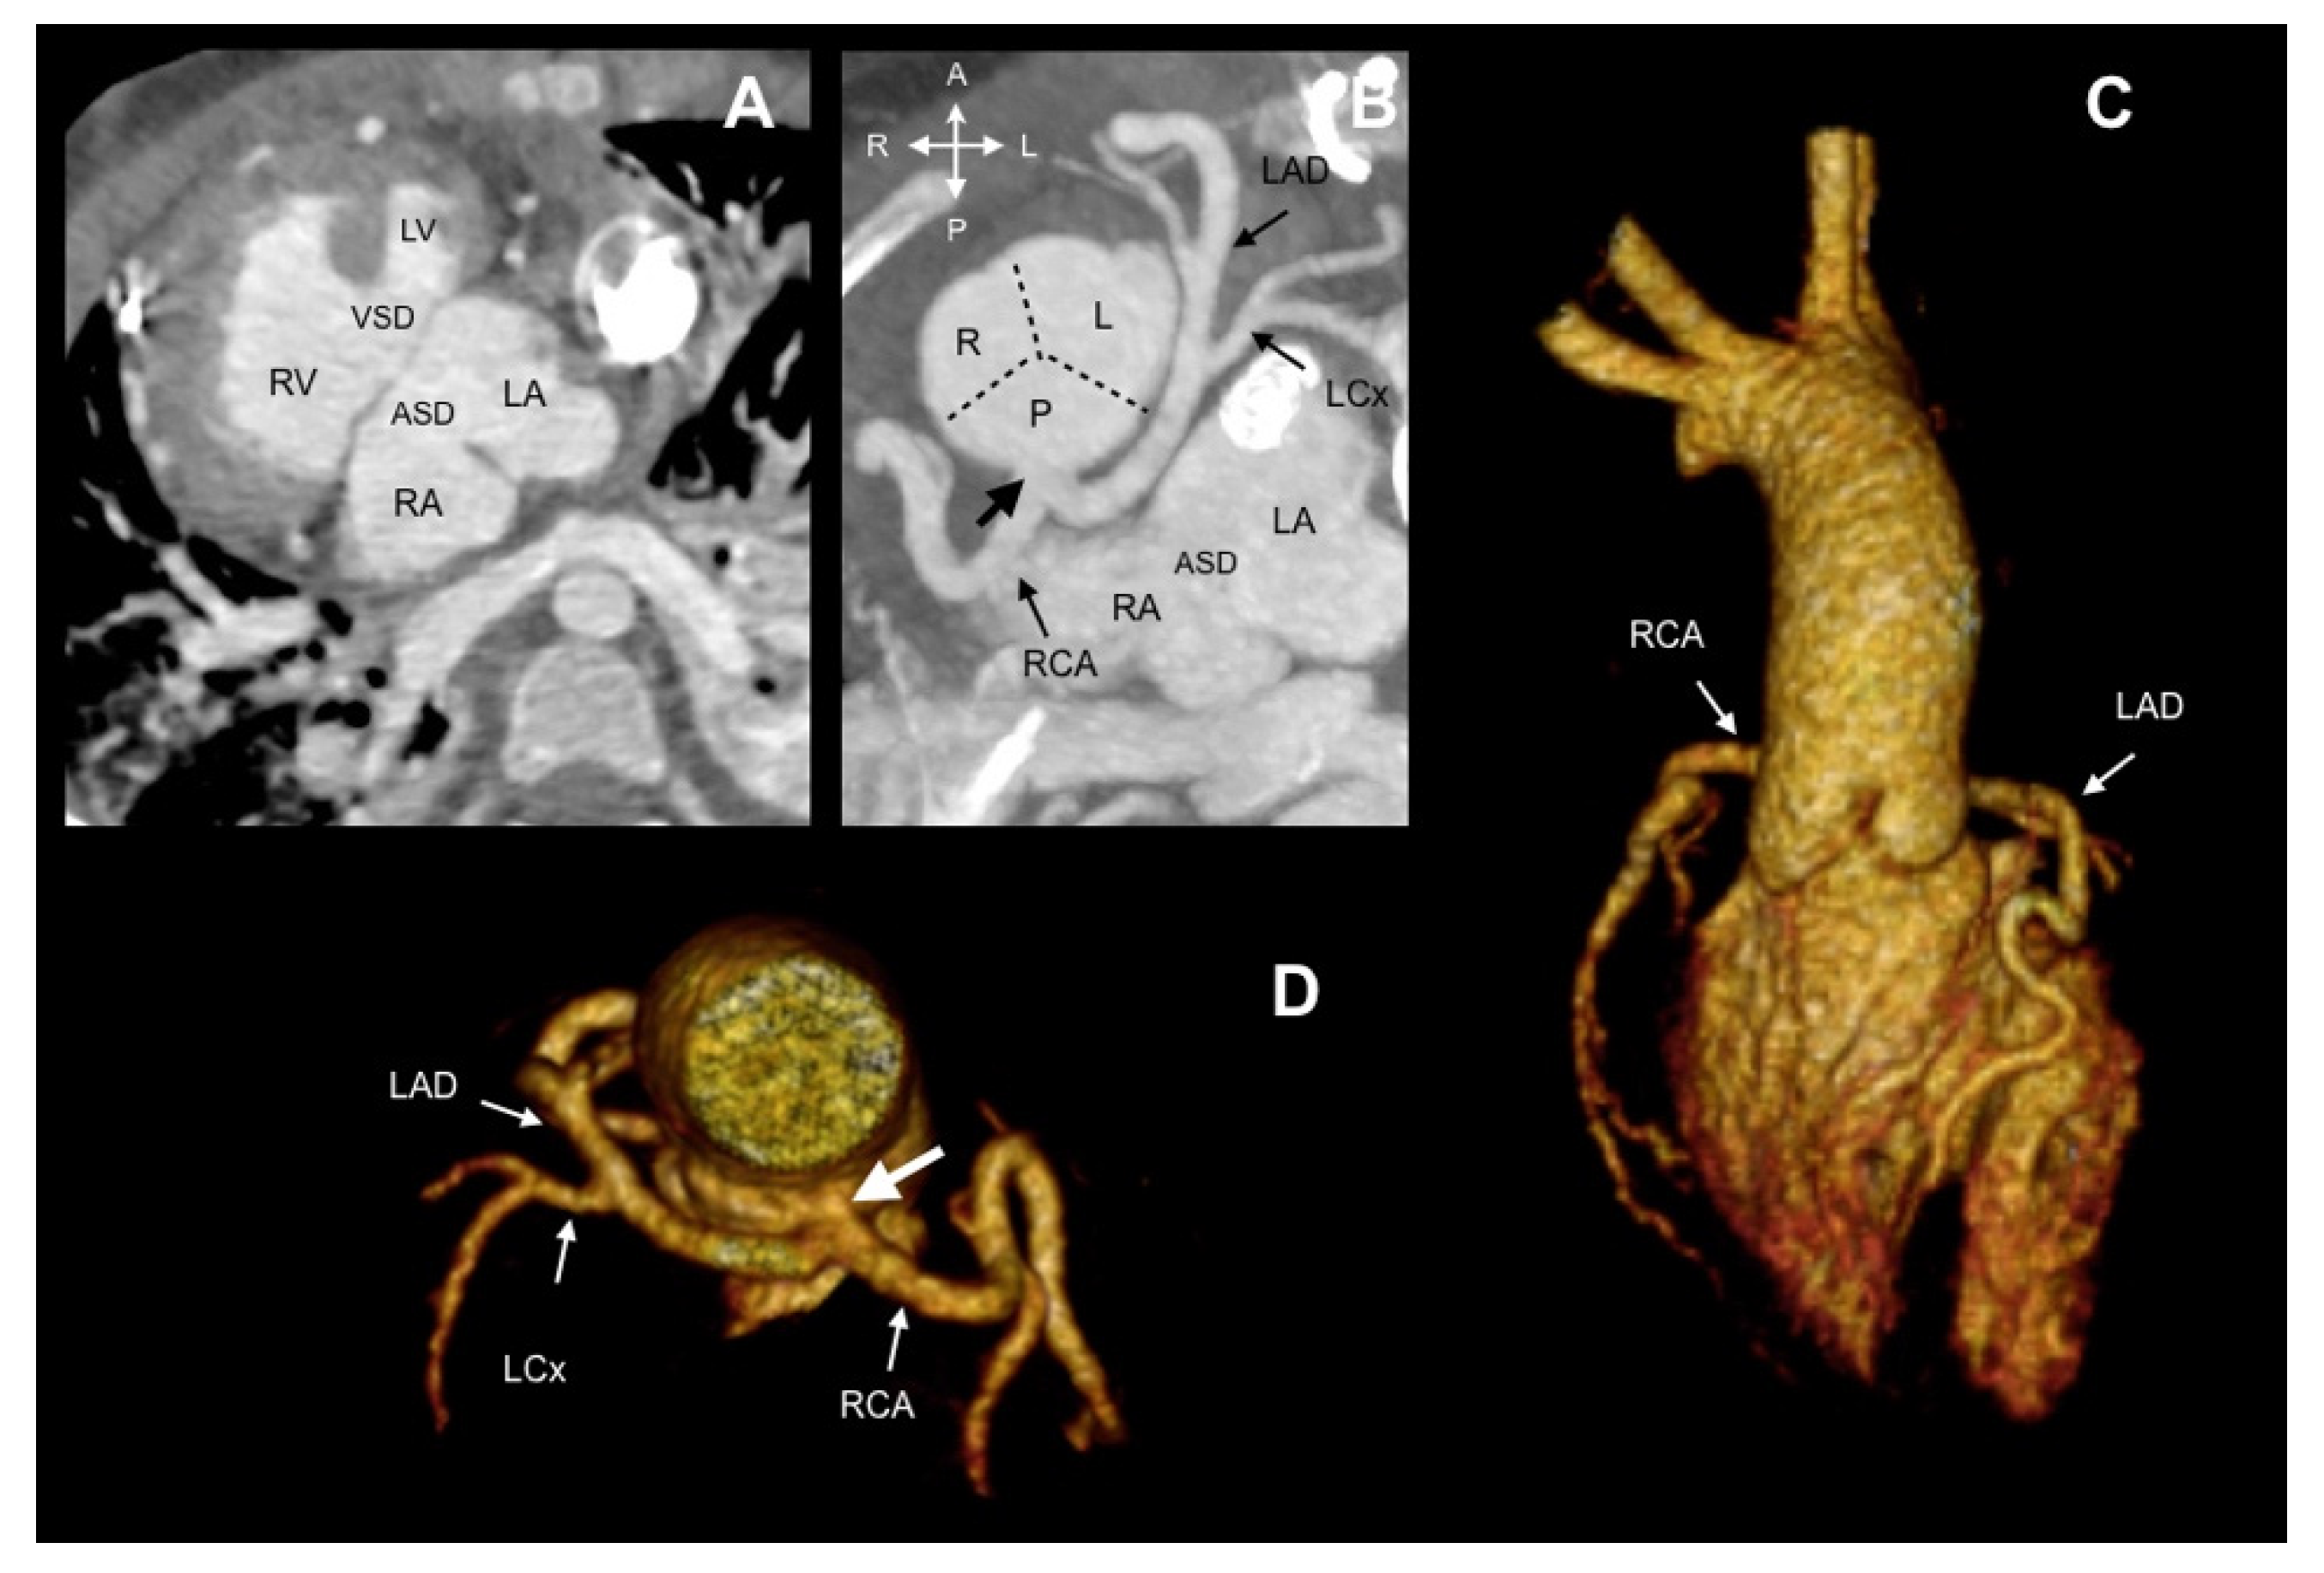

| 27 | F | 37Y | Atrial septal defect. Ventricular septal defect | Right posterior | 2R*LCx | LIIB | Anomalous origin of RCA from LAD |

| 28 | F | 51Y | Left ventricular non-compaction | Right posterior | 2RLCx | LIIA | Anomalous origin of RCA from LAD |